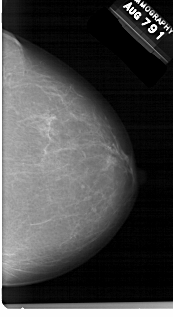

A_1541_1.RIGHT_MLO

RIGHT_MLO LINES 6541 PIXELS_PER_LINE 3076 BITS_PER_PIXEL 12 RESOLUTION 43.5 NON_OVERLAY